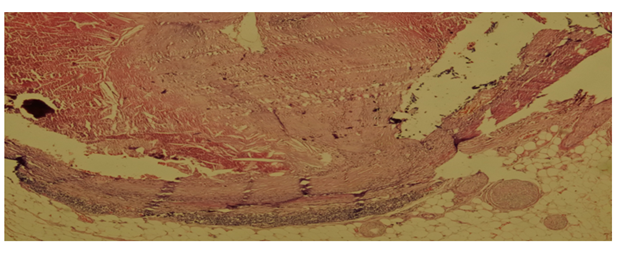

A 53 year old man complaining of headache was brought to emergency department but he was dead on arrival to hospital. The medical history gathered from family members was unremarkable except for a cerebrovascular accident four years ago. The autopsy had held in the Forensic Medicine Council of Adana Branch Morgue Department by two fellow forensic medicine specialists with the evaluation of a forensic pathologist and toxicologist. There were injection marks on left inguinal area and right antecubital fossa. Diffuse atheromatous plaques were seen in the aorta. There were numerous scar areas around the septum of the myocardium. There also was 1000 cc blood in the abdominal cavity escaped from the incomplete abdominal aortic rupture in the distal part with a false channel lumen between the intima and the media layer (Figure 1). Coronary dissection was noticed at right coronary artery and also a hematoma with a false channel lumen (Figure 2). Histopathologically, there were subadventitial dissection together with hematoma formation and luminal narrowing on the right coronary artery. The cause of death was given as co-effect of coronary artery dissection and aortic dissection (Figure 3).

Figure 3 Subadventitial dissection together with hematoma formation and luminal narrowing on the right coronary artery (HEX100).